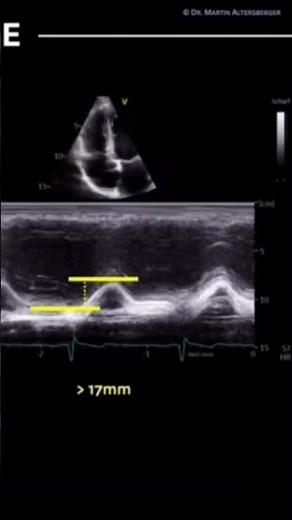

- Tapse

On Echo - Measuring Tapse

Echocardiogram - Tapse